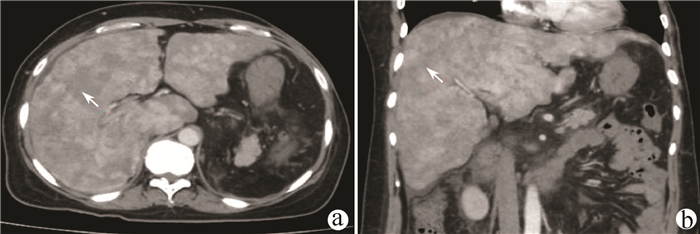

Primary splenic Kaposi sarcoma: A case report

Youchun LI, Guichao XU, Wenlei QI

2021, 37(7): 1668-1669. DOI: 10.3969/j.issn.1001-5256.2021.07.038

Abstract(727) HTML (199) PDF (2767KB)(19)

Abstract: